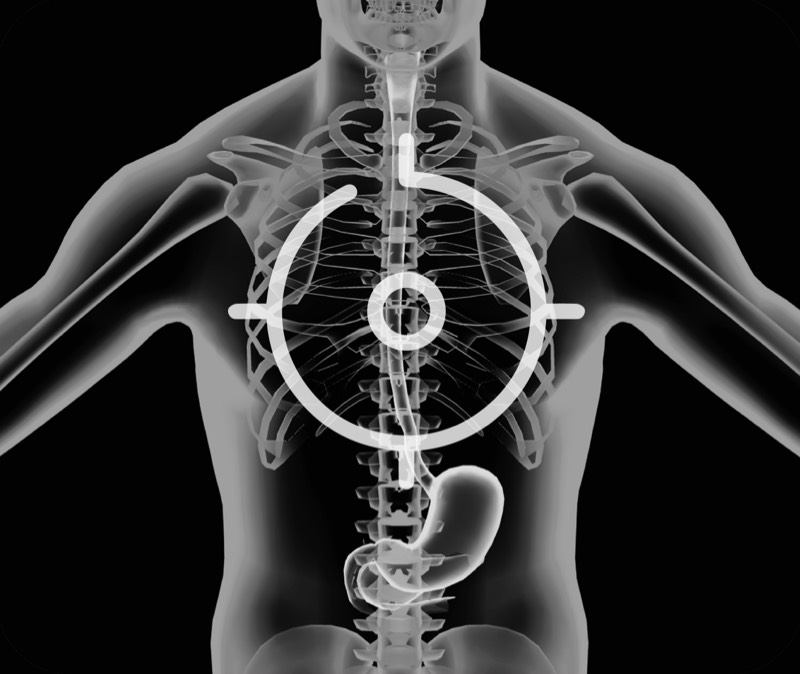

超声电子上消化道内窥镜